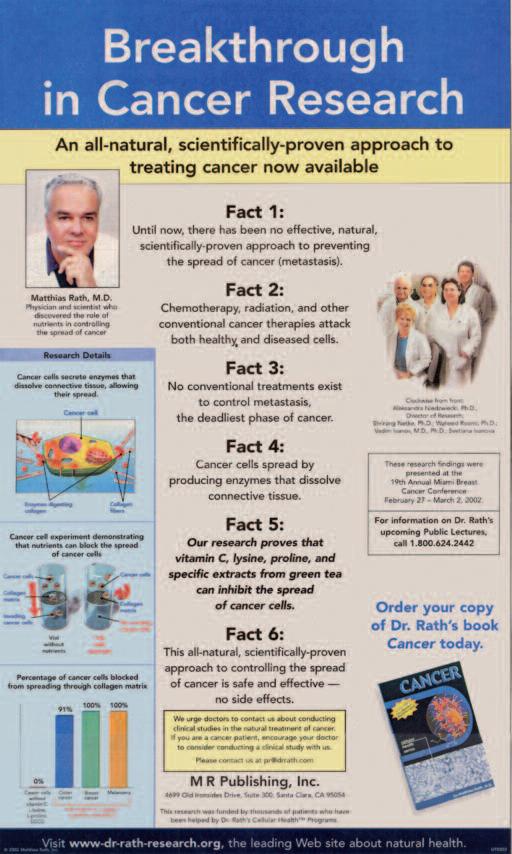

Solo due anni più tardi, nel 2001, avevamo già ottenuto le prime conferme scientifiche che dimostrano come é possibile inibire in modo naturale la propagazione delle cellule cancerogene. Abbiamo voluto condividere queste importanti scoperte con il mondo intero. L’8 marzo 2002, l’annuncio di questa scoperta medica é stato pubblicato su USA Today, il giornale con la più alta tiratura al mondo.

Riproduzione dell’annuncio sull’innovazione per il controllo naturale del cancro pubblicato l’8 marzo 2002 su "USA Today"